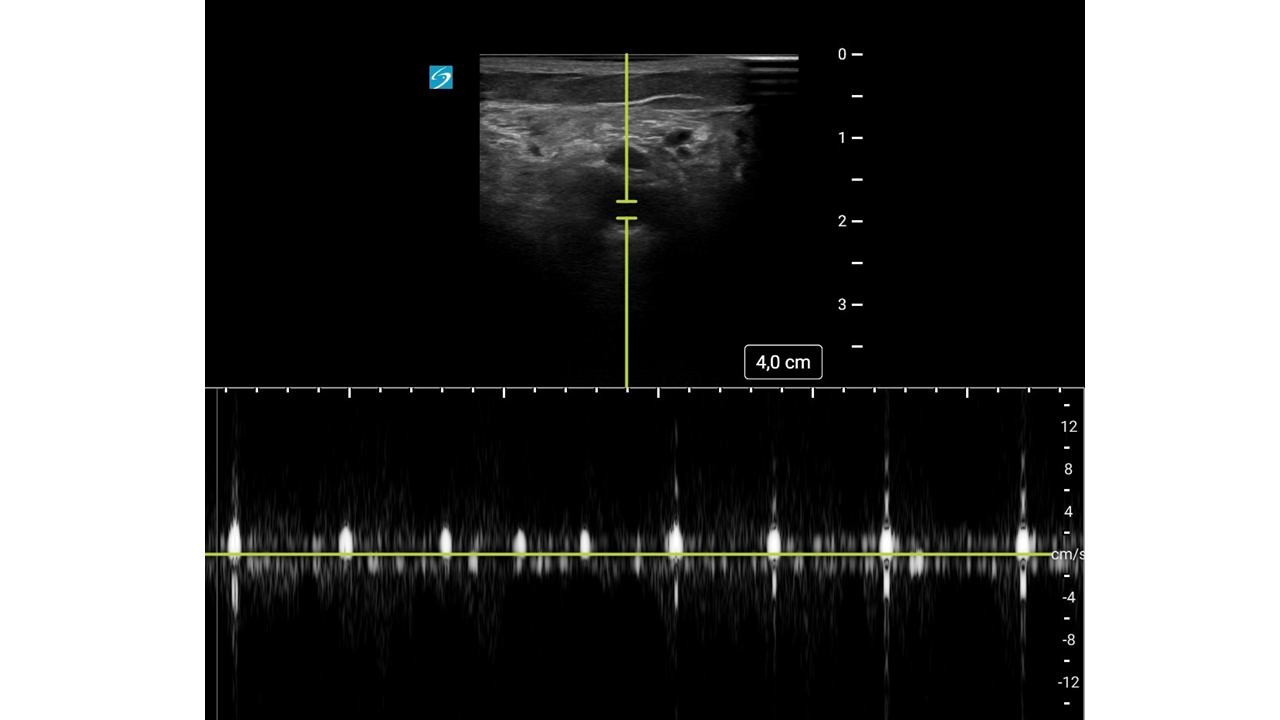

Con mejoría del dolor y pulso poplíteo dudoso, se duda del diagnóstico.

Con sospecha inicial de Isquemia Arterial Aguda (IAA), la mejoría clínica hace dudar abriendo el diagnóstico diferencial a una posible radiculopatía.

Con sospecha clínica de IAA, la ecografía vascular es clave para confirmar el diagnóstico. Su curva de aprendizaje es rápida, se puede utilizar en cualquier punto del sistema y permite derivar al paciente a un centro útil evitando demoras potencialmente fatales.